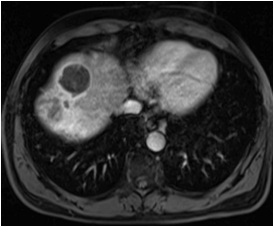

MRI 显示完全坏死,29个月没有复发。

男,49,巨大肝癌,DEB-TACE